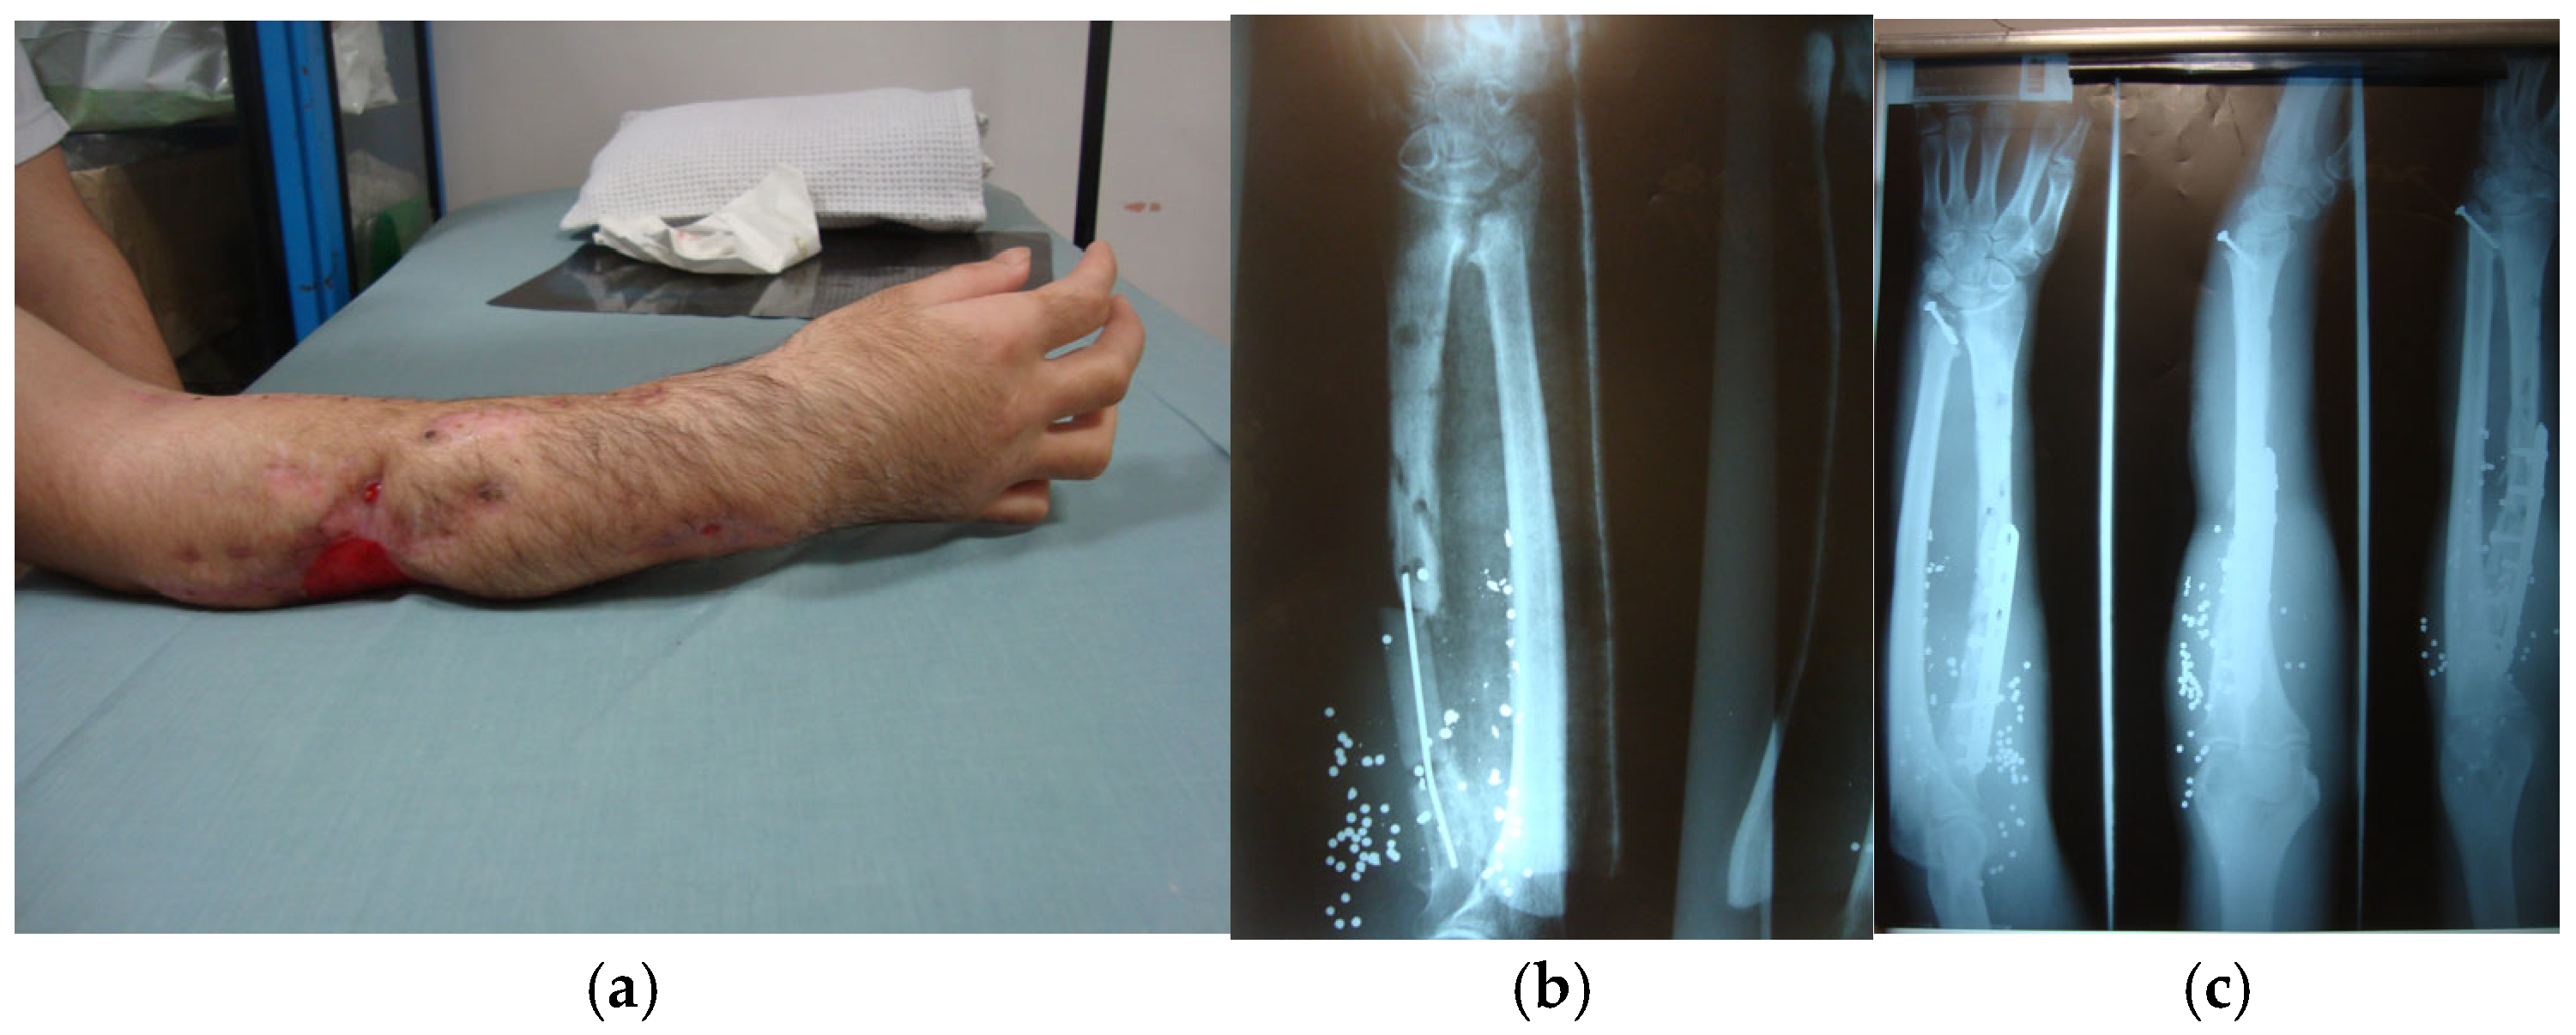

- Lin, J.S.; Rhee, P.C. Wrist and forearm fractures from ballistic injuries. Hand Clin. 2025, 41, 313–322. [Google Scholar] [CrossRef]

- Stefanopoulos, P.K.; Aloizos, S.; Mikros, G.; Nikita, A.S.; Tsiatis, N.E.; Bissias, C.; Breglia, G.A.; Janzon, B. Assault rifle injuries in civilians: Ballistics of wound patterns, assessment and initial management. Eur. J. Trauma Emerg. Surg. 2024, 50, 2741–2751. [Google Scholar] [CrossRef]